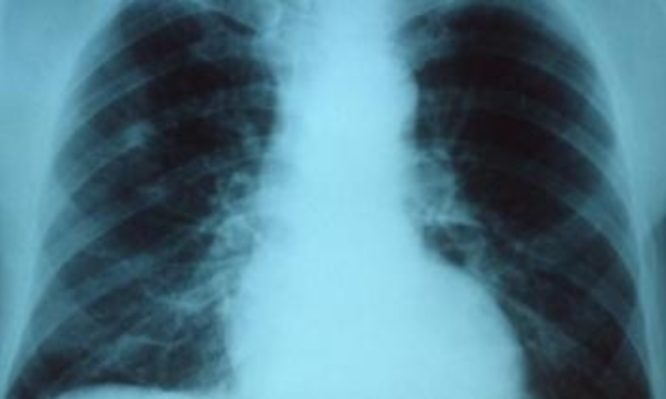

Οι λοιμώξεις του αναπνευστικού είναι πολύ συχνές, ιδιαίτερα το φθινόπωρο και το χειμώνα. Οι μολύνσεις στο στήθος μπορεί να είναι σοβαρές και να χρειάζονται άμεση αντιμετώπιση. Ωστόσο, πολλές μολύνσεις στο στήθος σε κατά τα άλλα υγιείς ανθρώπους δεν χρειάζονται αντιβιοτικά φάρμακα.

– Η οξεία βρογχίτιδα είναι μια λοίμωξη των μεγάλων αεραγωγών των πνευμόνων (βρόγχοι). Είναι κοινή και συχνά οφείλεται σε ιογενή λοίμωξη.

– Η πνευμονία είναι μια σοβαρή λοίμωξη του πνεύμονα.

Τα κύρια συμπτώματα είναι ο βήχας, η δυσκολία στην αναπνοή και ο πόνος στο στήθος. Μπορεί επίσης να έχετε πονοκεφάλους και πυρετό. Τα συμπτώματα της οξείας βρογχίτιδας και της πνευμονίας μπορεί να είναι παρόμοια, αλλά τα συμπτώματα της πνευμονίας είναι σοβαρότερα.

Η βρογχίτιδα προκαλείται συνήθως από έναν ιό, και σπάνια αντιμετωπίζεται με τη λήψη αντιβιοτικών. Η πνευμονία, σε αντίθεση με βρογχίτιδα, συχνά προκαλείται από ένα βακτήριο και μπορεί να χρειαστεί θεραπεία με αντιβιοτικά.

Αν η πνευμονία είναι πολύ σοβαρή, μπορεί να χρειαστεί εισαγωγή σε νοσοκομείο.